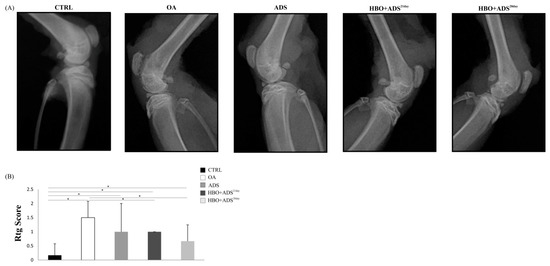

2.2. Radiography of OA

4.6. Radiographic Analysis of OA